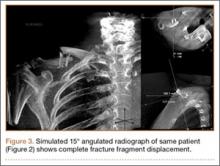

Retrospective review of our cohort’s initial radiographs revealed 1 case in which the patient’s completely displaced midshaft clavicle fracture would not have been diagnosed solely with an AP horizontal image. Cortical contact was seen on a standard AP clavicle radiograph (Figures 2A, 2B), and a 15° tilt radiograph created from 3-D fluoroscopy scan showed complete fracture fragment displacement (Figure 3). A change in fracture classification from partially displaced to fully displaced could alter the type of management used by a treating surgeon.